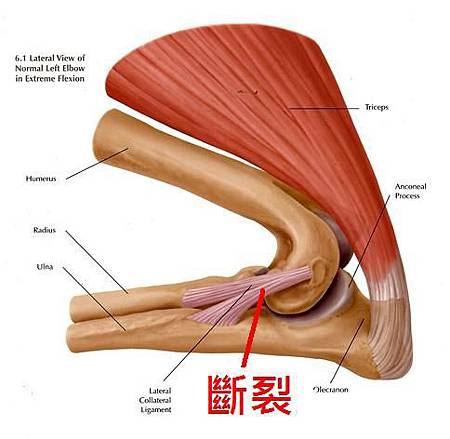

哈利來醫院時右手手肘向外脫出,無法著地。X射線檢查發現右側手肘脫臼需要進行韌帶重建手術。韌帶重建術是經由手術在原本韌帶生成處的骨頭兩端,先置入螺釘固定,再將人工韌帶緊綁於螺釘兩端,替代原來斷掉的韌帶。

創傷造成肘關節脫臼在任何年齡及品種的犬隻身上皆會發生。通常病畜會有創傷或跟其他犬隻打架的經驗。肘關節脫臼比較常見的是向外脫臼。肘部的創傷可能導致側韌帶撕裂或斷裂,更嚴重的創傷可能造成附近伸肌或屈肌斷裂,甚至傷害到軟骨。

發生肘關節脫臼時,會出現急性的跛腳,患肢無法負重且呈現屈曲的姿勢,前肢會呈現外展且向外旋轉的情形。於X光下,側照可以看到肘關節的關節腔空隙看不清楚,有骨頭重疊的感覺。有時候創傷也可能造成肱骨髁狀突的骨折。